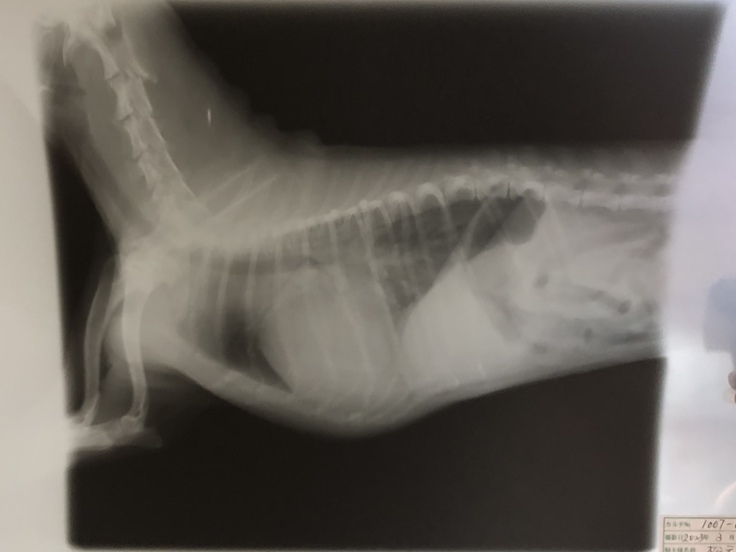

肺水腫を起こした際のレントゲンです。